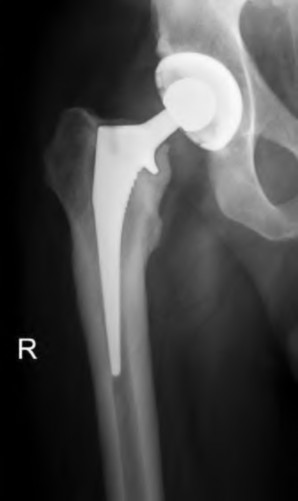

A 67-year-old man who underwent total hip arthroplasty (THA) 4 years ago fell on to his right hip. His pre-injury right hip film is seen in Figure A while films of his current injury are seen in Figures B and C. Prior to the fall he had no thigh or hip pain. His ESR and CRP are within normal limits. During intraoperative assessment, the acetabular and femoral stems are found to be well fixed. What is the next best course of action?

This patient has a periprosthetic hip fracture at the level of the stem with a stable prosthesis, indicated open reduction and internal fixation as the treatment of choice.

The Vancouver Classification can be helpful in clinical decision-making regarding fixation versus revision of periprosthetic hip fractures of the proximal femur. A stable implant, by nature, does not need to be revised in the setting of adequate bone stock for fixation, but the ultimate test of stability should be in the operating room. Many fixation strategies are appropriate, but many implants include locking plate fixation for concerns of stress-shielded bone around the implant as well as use of unicortical fixation at the level of the stem.

Illustration A shows a possible fixation construct for this patient's fracture. The Vancouver Classification is seen in Illustration B and Illustration C represents an algorithm for treatment options.